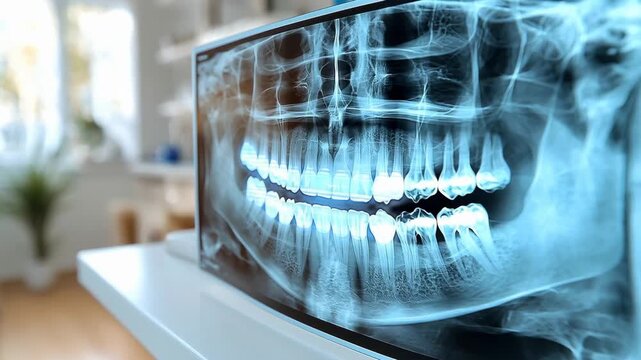

Review Your Existing X-rays

E-mail us your current x-rays and the dentist will review them to make a preliminary diagnosis.